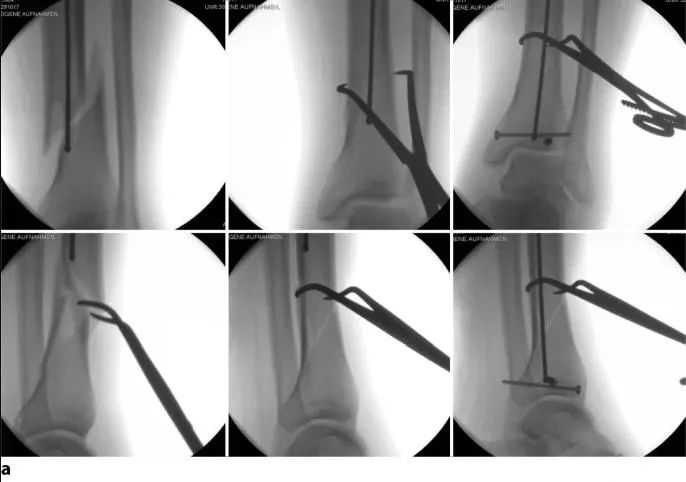

Sanajan kitu, dina kalolobaan kasus, sababaraha maneuver réduksi diperlukeun pikeun ménta sarta ngajaga repositioning nyugemakeun tina fractures ieu. Lamun garis narekahan téh basajan tur angled, adzab basajan reset clamps atanapi coaptation clamps, disimpen percutaneously, bisa dipaké pikeun ménta jeung mertahankeun reset salila nailing. Lamun clamp nyaeta inadequate atawa pesawat narekahan teu nginjeumkeun sorangan ka clamping, sari atawa blocking screws bisa mantuan nyegah kapindahan sarta malposition (gambar 15). screws ieu disimpen posterior ka posisi paku nu dipikahoyong dina pintonan gurat jeung gurat ka posisi kuku dipikahoyong dina pintonan anterior-posterior. panempatan ditangtoskeun tina screws ieu pikeun reset alus bisa jadi nangtang.

Téhnik séjén anu pohara efektif nyaéta fiksasi samentara tina narekahan dina posisi anatomis (Gbr. 16). Biasana piring tubular sempalan leutik kalawan dua atawa tilu screws konci cortical tunggal bakal nahan narekahan ngurangan salila persiapan terusan akar jeung sisipan paku. piring bakal ngadalikeun duanana displacements. piring kudu ditinggalkeun di tempat salami euweuh celah tetep pikeun nyegah leungitna réduksi nu biasana lumangsung sanggeus panyabutan plat. piring ieu kalawan screw cortical tunggal teu kaku jeung moal mangaruhan stabilitas relatif kuku. Téhnik reset plate tiasa dianggo pikeun narekahan anu kabuka sareng ditutup.

angka 16 A plat ngonci leutik ku screw cortical tunggal tiasa didapet tur dijaga dina reposition anatomis. Dina kalolobaan kasus, piring kudu ditinggalkeun di tempat sanggeus nailing. a deformity valgus awal tina narekahan tibial proksimal. b A pelat narekahan leutik ku screw cortical tunggal disimpen medially pikeun ménta sarta ngajaga repositioning narekahan salila nailing. c piring teu dipiceun sanggeus nailing sabab nyadiakeun stabilitas tambahan